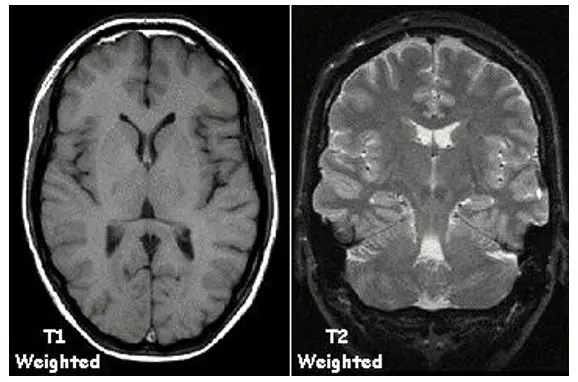

在射频磁场作用下,氢原子核微粒的集体磁化向量可以分为两个分支:垂直z分量,水平xy分量。射频磁场的作用时间通常是非常短暂的,射频磁场撤去后,在自由进动阶段,磁化向量经过一个称为“弛豫”的过程,恢复它的原始静止位置。弛豫过程的特性由时间常数T1和T2来描述纵向弛豫 (z) 和横向弛豫(xy) 的特征。人体大脑和身体不同组织或组织液具有不同的纵向和横向弛豫特性,核磁共振成像技术最为关键的物理原理就是利用了这一点的特性分别不同的脑组织结构和功能。另外,NMR信号强度与样品中氢核的密度有关,人体中各种组织间含水比例不同,即含氢核数的多少不同,他们之间就存在NMR信号强度的差异。利用这种差异作为特征量,可以把各种组织分开,这就是氢核密度的核磁共振图像。

图8. 磁共振扫描中大脑T1加权成像和T2加权成像